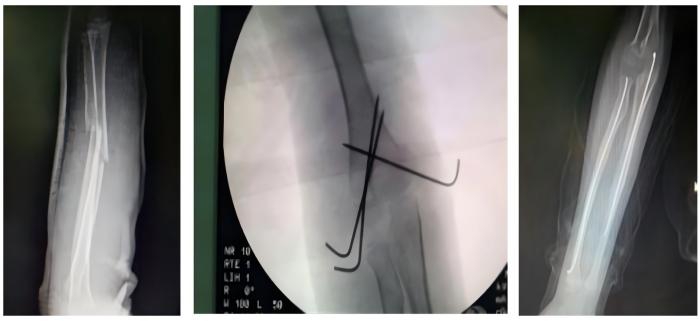

常规开展人体各部位骨折、脱位的修复重建。业务亮点:①伦理片骨科对于复杂胫骨平台的治疗方法获得国际“平台大师”罗从风教授的高度肯定,并将其编入胫骨平台骨折诊疗教程。②伦理片骨科通过Stoppa入路,结合传统入路的精髓,治疗复杂骨盆骨折,并在福建省率先使用骨折微创内支架治疗骨盆前环损伤。③对于四肢长管状骨骨折,伦理片骨科通过几个1-2CM的手术切口,闭合复位骨折,微创插钉,不破坏骨折端软组织及血运。不但减小了手术创伤,还提高了愈合速度。④伦理片骨科于国内首创使用“微创钛揽捆扎固定”,治疗肩锁关节脱位,完美解决传统手术手术创口大,肩关节活动差,内固定撞击等诸多缺点。

骨折的微创固定手术